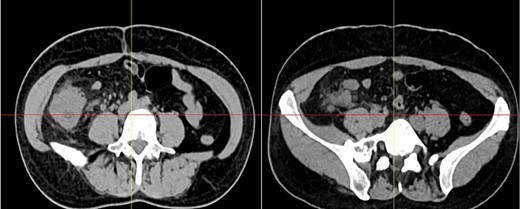

Pathology reported a 10 × 6 cm tumor. It expanded from the cecum into the ileocecal valve and had a soft exterior. Microscopically, it was formed by multiple myofibroblastic spindle cells with borderline malignancy. Numerous plasma cells and lymphocytes were also seen (Fig. 2). Immunohistochemistry was positive for actin and ALK (Fig. 3). Margins were free of tumors, and all lymph nodes were negative for invasion. Inflammatory myofibroblastic tumor was the final diagnosis.

The mass is completely removed from the patient; it involves the cecum and ileocecal valve.